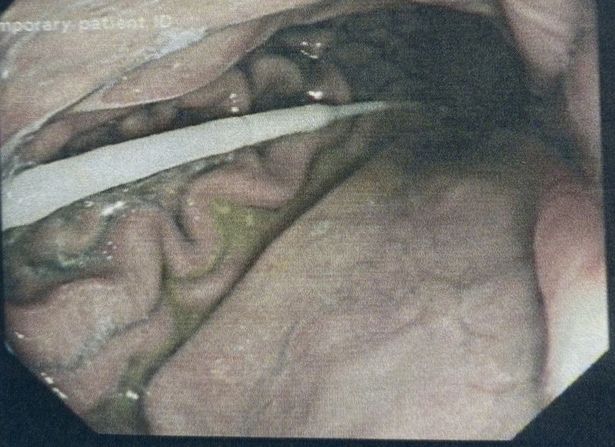

بوبي لي، سيدة تبلغ من العمر 31 عامًا، وتعيش بإحدى أحياء المملكة المتحدة، كانت بوبي تعاني من النزلات المعوية التي جعلتها تخضع لاختبار مسح الكورونا، وأحضرت الجهاز الماسح إلى المنزل واستخدمته بنفسها حتى سقط إلى أمعائها، جهاز يبلغ طوله 6 بوصات، وهرولت بوبي إلى المستشفى للحصول على الإسعافات الأولية والخضوع لإنقاذ الأطباء، حيث تفاجئ الأطباء من الحادثة، وأجريت العمليات الجراحية للسيدة بوبي لإخراج الماسح الذي وصل للأمعاء.

قالت بوبي لي، الأم العزباء، إن استخدام الماسح لتحليل الإصابة بفيروس كورونا، ولقد وضعت الماسح بفمي ثم انزلق إلى البلعوم فقررت ابتلاعه لأنني كنت أشعر بالاختناق وضيق التنفس.

وأوضحت الأم العازبة، أنه يعد من الأمور الصعبة التي تمر على حياة الفرد وبالتحديد إذا كنت تمتلك طفلًا صغيرًا، لقد شعرت بضيق التنفس بعد ابتلاع الماسح حيث بلغ طوله من فمي موصولا إلى أمعائي، وذهبت للمستشفى لأنني كنت أعتني بطفلتي مما جعلني اهرول سريعًا خوفًا من تدهور حالتي الصحية والطفلة رضيعة صغيرة.